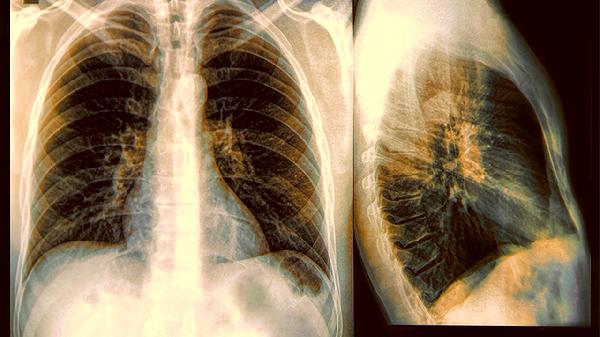

43岁男子从不吸烟却患上肺癌,究竟为何?

奶奶因肺癌去世的家族史,可能藏在你23对染色体某段脆弱基因里。EGFR或ALK这些听起来像WiFi密码的基因突变,会让癌细胞增殖速度快过双十一销量,有亲属病史的建议把CT纳入年度体检豪华套餐。